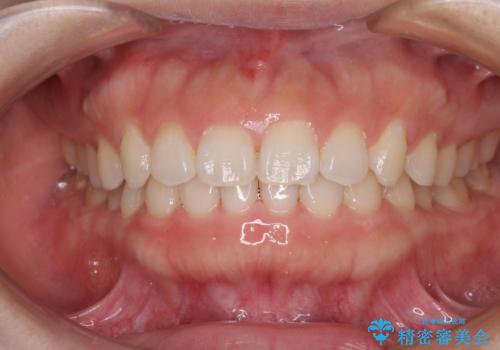

- 前歯のデコボコを治したいとのことで来院された患者様です。

上下顎ともに歯列全体の側方拡大とIPR(歯と歯の間を削る)によってデコボコが解消するように設計し、インビザラインにより治療を行うこととしました。

1日22時間の装着時間をしっかり守ってくださったので、1年程度で治療を終えることができました。

1セットのマウスピースで概ね治療を終えたのですが、前歯僅かな叢生が残ったため、2セット目のマウスピースで仕上げました。

気にしていた口元の印象が改善され、患者様には大変満足していただきました。